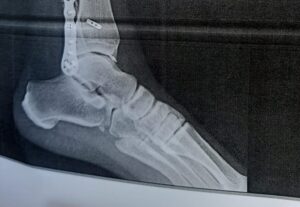

Daniel Luque estará mañana en el túnel del Coliseo de Nimes. La decisión se ha tomado a primera hora de este jueves tras pasar consulta y revisión médica y tras permanecer tres días en completo reposo. Durante la revisión, los facultativos han hecho unas radiografías a Daniel Luque -que se adjuntan- donde se aprecia abiertamente […]